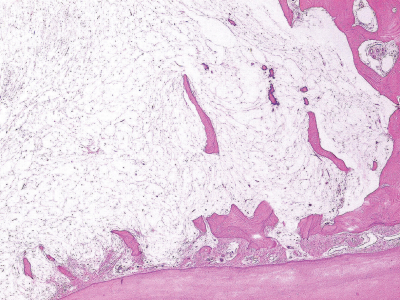

42歳の男性。下顎右側大臼歯の動揺を主訴として来院した。3年前から同部の歯肉の腫脹に気付き、徐々に歯が動揺するようになったという。初診時のエックス線画像、CT及び生検時の H-E 染色病理組織像を別に示す。